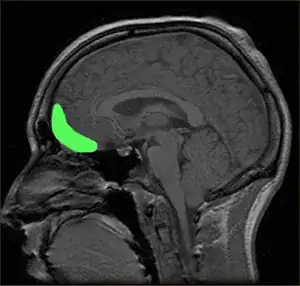

Orbitofrontal Cortex

Model and sagittal MRI of the orbitofrontal cortex

The other region commonly implicated in association with APD and antisocial behavior is the orbitofrontal cortex (OFC) (Blair and Frith, 2000). For example, Völlm et al. (2004) reported fMRI evidence for a go-no-go task suggesting that APD patients exhibited reduced OFC activity for response inhibition as compared with controls. Dinn and Harris (2000) reported that "APD subjects showed greater neuropsychological deficits on measures sensitive to orbitofrontal dysfunction in comparison to control participants." The OFC seems to be associated with increased impulsivity and risk-taking via deficient response inhibition.